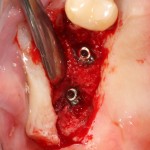

Имплантация и остеопластика: вместе или врозь? Часть II плюс Ankylos, плюс Geistlich